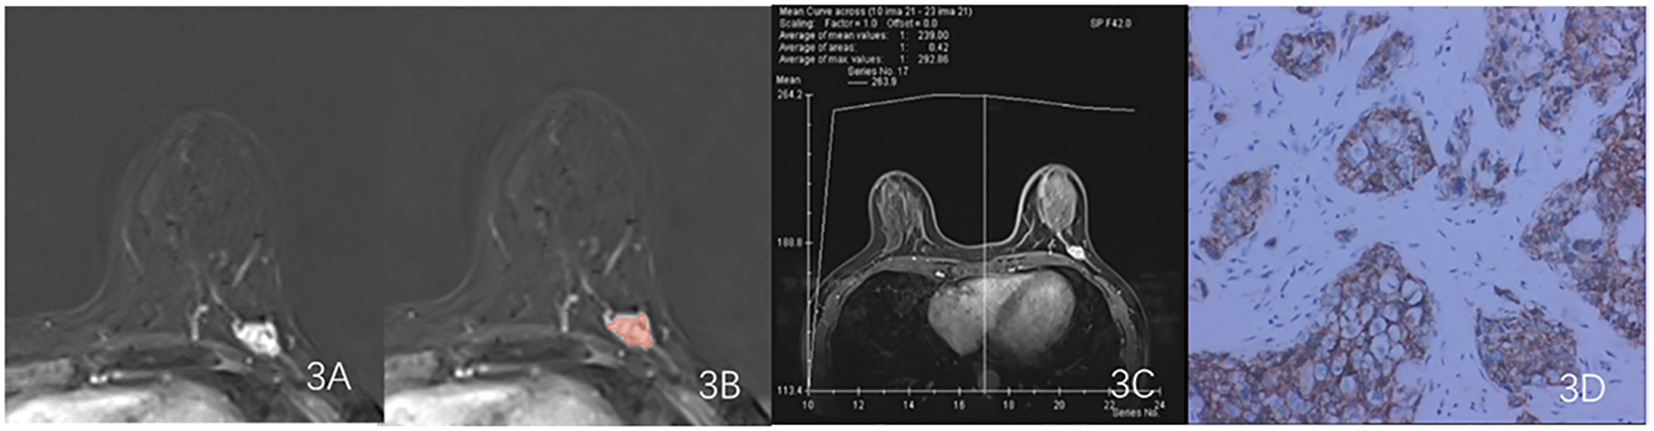

Figure 3. Results obtained from a randomly-selected HER2 - case. (A) Subtraction image of pre- and post-contrast scans. (B) Enlarged image showing the ROI (red region) delineated manually by an experienced radiologist, then, the segmentation was examined by another radiologist. (C) TIC curve (platform type) of the DCE image. (D) Pathology results showing IDCS (HER2- gene confirmed by IHC).

Export the DCE phase 2 images from the Picture Archiving and Communication System (PACS) in DICOM format (Figure 1). A radiologist, blinded to the pathological results, manually delineated the tumor regions using 3D Slicer 4.11 software, avoiding the necrotic and cystic areas of the lesion. If the patient had multiple lesions, the largest lesion was selected for delineation (Figures 2, 3). Using a simple random sampling method, 16 cases were selected from 118 patients. Another radiologist, blinded to the pathological results, re-delineated the regions of interest for reproducibility analysis using the intraclass correlation coefficient (ICC).